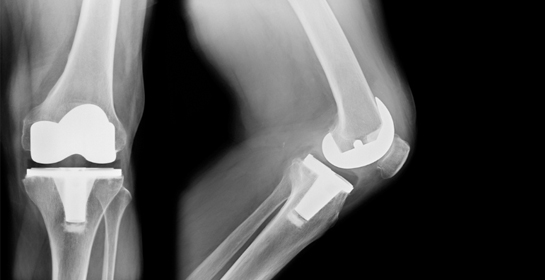

Knee Replacement Surgery

What is Knee Replacement Surgery?

Knee replacement surgery, also known as knee arthroplasty, is a procedure to relieve pain and restore function in damaged knee joints. It involves replacing the worn-out or diseased joint surfaces with artificial implants, improving mobility and quality of life.

1. Total Knee Replacement (TKR)

Icon Involves replacing the entire knee joint with prosthetic components.

Icon Recommended for severe arthritis affecting the whole joint.

Icon Restores full knee function and reduces chronic pain.